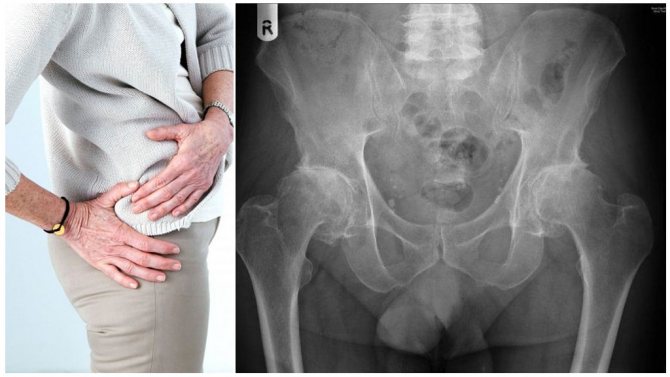

Коксартроз (артроз) тазобедренных суставов – это патология, при которой происходят разрушительные процессы в хрящевой и костной структуре сочленения.

Тазобедренный сустав (ТБС) является самым крупным сочленением во всем теле человека, поэтому он испытывает каждый день колоссальную нагрузку во время движения человека и даже в состоянии покоя.

Коксартроз – это постепенное разрушение сустава, являющееся следствием истончения хрящевых тканей, ввиду чего кости соприкасаются друг с другом, и это провоцирует травму. Патология бывает односторонней и двусторонней. В последнем случае суставы поражаются постепенно. Опасно заболевание тем, что на начальных этапах его развития настораживающие признаки практически отсутствуют.

В нормальном состоянии тазобедренный сустав должен выглядеть, как шарнир. При этом плавность движений обусловлена специальной смазкой.

Но при появлении патологии ее состав и качество ухудшается. При этом кости касаются друг друга , что способствует истончению хряща и к деформации.